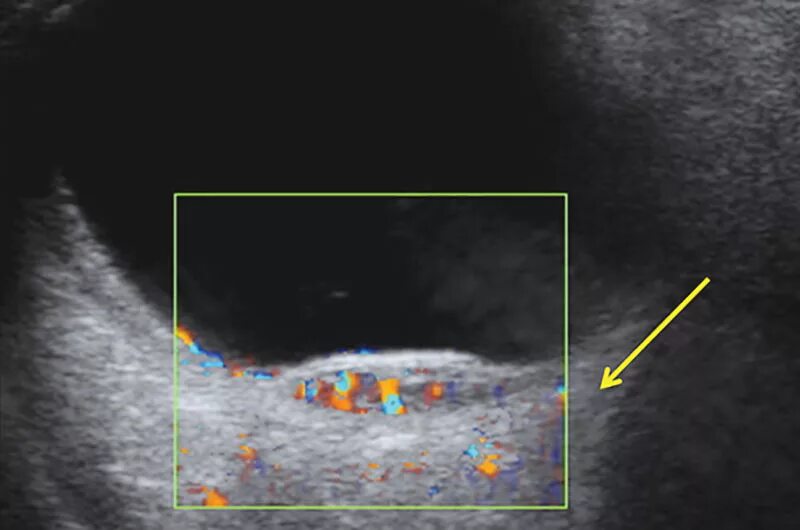

Метастазы в паховых лимфоузлах